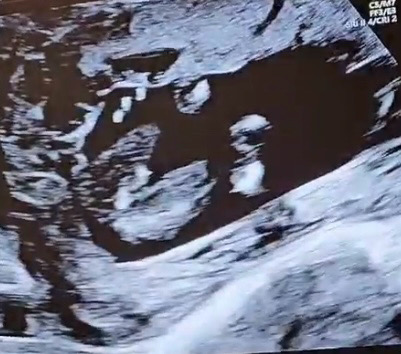

15주 5일차 성별 알수있을까요?

쌤이 힌트를 안주시고, 20주때 확실해지면 말씀해주신다는데 너무 궁금해서요ㅠ 한번 봐주세요.!!

이 사진으로는 알아보기가 어려운것같아용ㅠㅠ

저두 저게 가운데 무엇인가가 탯줄인지 먼지 모르겠더라구욤...ㅠ 댓글감사해요ㅎㅎ